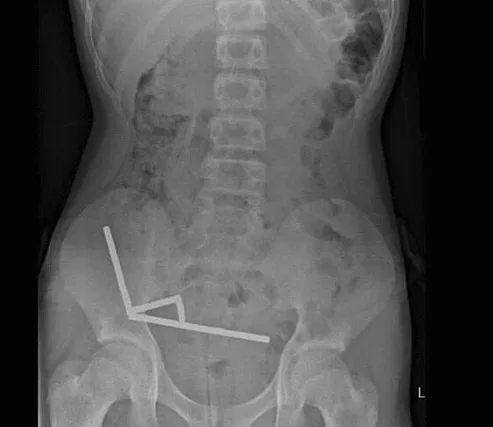

צילום הרנטגן חשף תמונה מדאיגה – המגנטים התקבצו והתחברו יחדיו בחלקים שונים של המעי. הניתוח כלל הסרה של הרקמות המתות וחילוץ של כל המגנטים. הנער שוחרר הביתה לאחר 8 ימים של אשפוז.